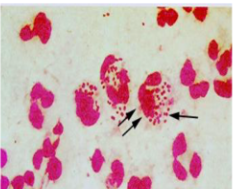

bacteria in PMNs-N. meningiditis

bacteria in PMNs-S. pneumo or S. agalactiae (clusters)